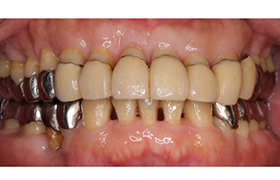

Before

After